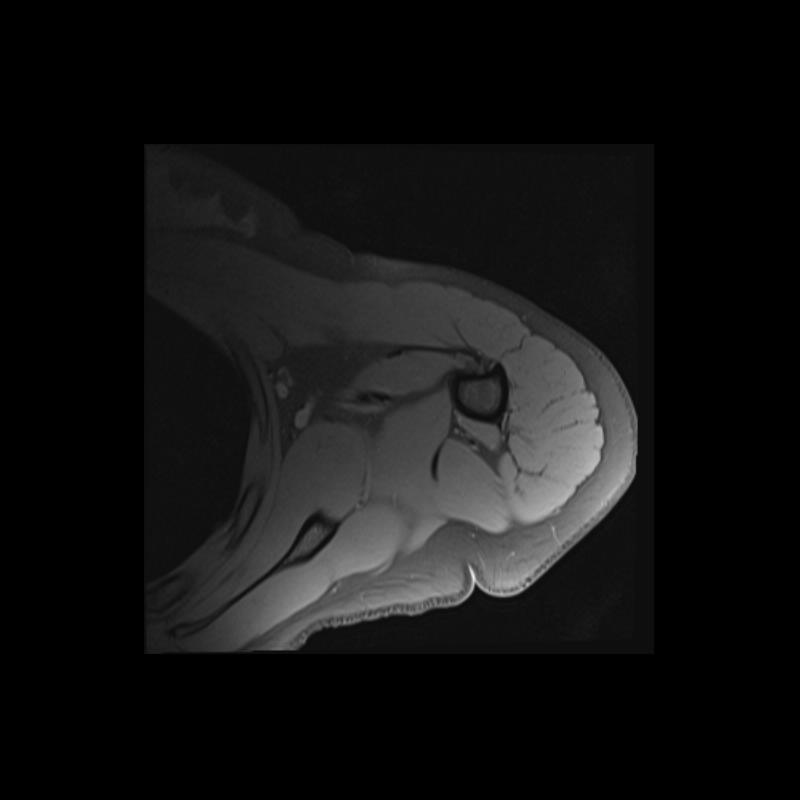

Shoulder MRI Anatomy